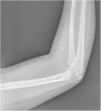

Varón de 9 años sin antecedentes de interés. Consulta por una mancha azulada en el brazo derecho que tenía desde el nacimiento, con crecimiento de la misma. Dolorosa en el último mes. En la exploración destacaba una lesión azulada, gomosa y tortuosa que se extendía desde el dedo 1.° de la mano derecha, hasta la zona periaxilar, abarcando la cara ventral de brazo y antebrazo (fig. 1). En la región antecubital, las más voluminosa, se palpaban varios nódulos firmes y dolorosos. Ante la demora de la ecografía, realizamos una radiografía que mostró varias calcificaciones que coincidían con los puntos dolorosos (fig. 2). La ecografía fue informada de lesión de bajo flujo. La analítica mostró el dinero D elevado. El diagnóstico fue malformación venosa con flebolitos realizando tratamiento con ácido acetilsalicílico 50mg/día hasta desaparición del dolor pasado un mes.